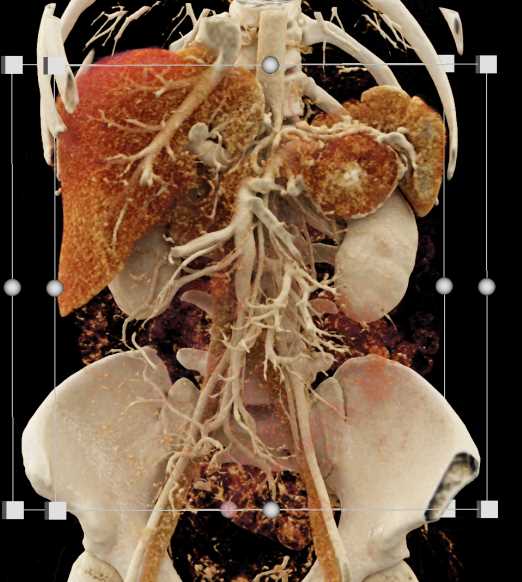

Neuroendocrine Tumor Pancreas